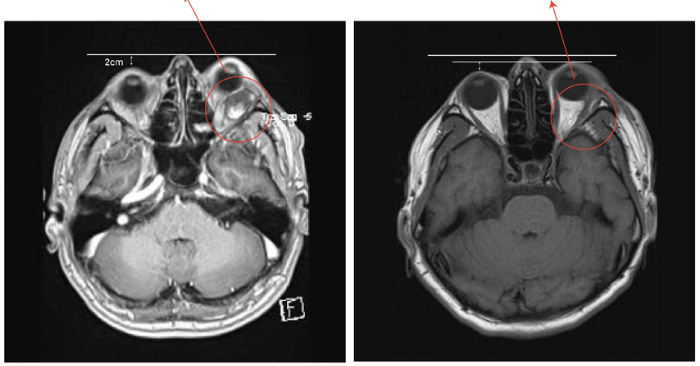

Sự lo lắng của gia đình đã thúc đẩy anh tìm kiếm giải pháp y tế chuyên sâu tại Việt Nam. Qua lời giới thiệu từ bạn bè về những ca bệnh phức tạp đã được điều trị thành công, anh T. quyết định đến Bệnh viện Đa khoa Quốc tế Nam Sài Gòn để cầu cứu. Sau khi thực hiện kiểm tra lâm sàng và chụp MRI, các bác sĩ tại khoa Ngoại thần kinh – Cột sống đã phát hiện một khối u kích thước lớn đang âm thầm phát triển sâu phía sau nhãn cầu trái, liên tục chèn ép dây thần kinh thị giác của bệnh nhân.

Để đảm bảo độ chính xác tuyệt đối, ê-kíp phẫu thuật đã ứng dụng hệ thống kính vi phẫu TIVATO 700 hiện đại để phóng đại các cấu trúc siêu nhỏ trong hốc mắt. Trong hơn bốn giờ đồng hồ căng thẳng, các bác sĩ đã tỉ mỉ bóc tách khối u dài khoảng 4cm ra khỏi các mô xung quanh mà không cần phải thực hiện cắt xương hốc mắt. Kết quả giải phẫu bệnh sau đó xác định đây là u mạch máu dạng hang lành tính, giúp xua tan mọi lo lắng về tâm lý cho bệnh nhân và người thân.